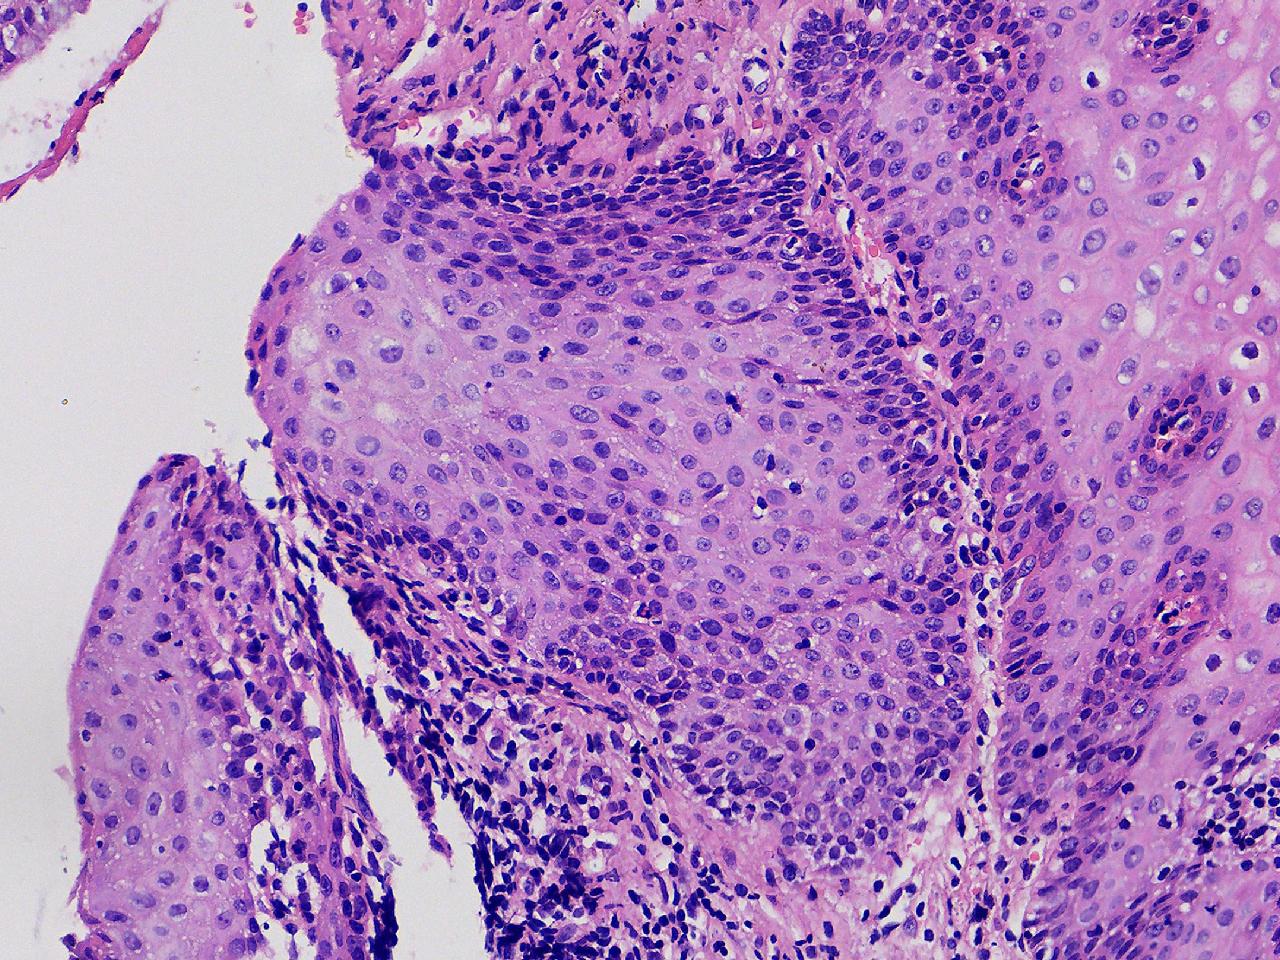

此处鳞化腺体够不够CIN1级? 应该不到CIN2级吧?

性别

女

年龄

47岁

临床诊断

宫颈活检组织

一般病史

宫颈活检,HPV不详。

标本名称

宫颈活检

大体所见

宫颈活检组织。

图1

图2

图3

图4

鳞化

二级没有,好像有hpv感染,如果有hpv高危阳性,建议低度